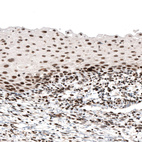

Immunohistochemical staining of human thyroid gland shows strong nuclear positivity in glandular cells.